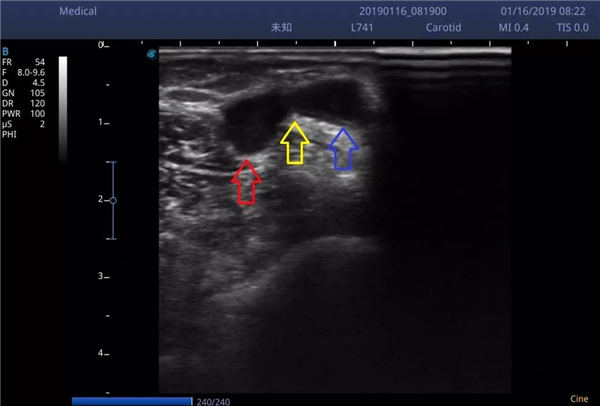

虽然超声仍可见桡动脉(红色箭头)、贵要静脉(蓝色箭头)、内瘘口(黄色箭头)存在轻度狭窄↓↓↓,但血流通畅不影响透析。